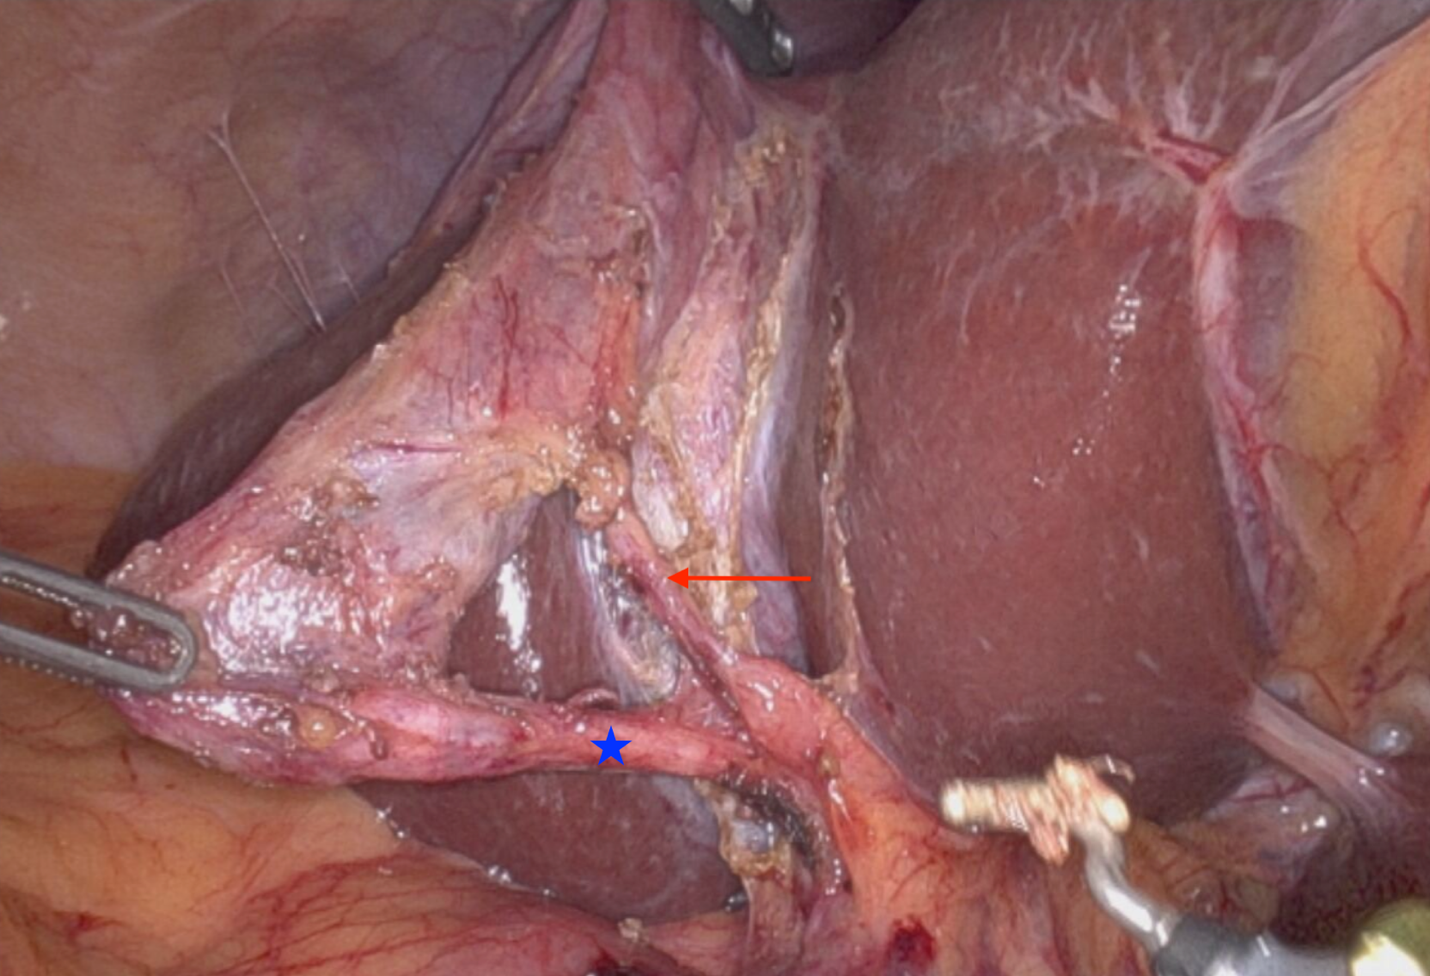

Three weeks later, the patient presented for a robotic-assisted laparoscopic cholecystectomy and epigastric hernia repair. Upon abdominal entry, numerous filmy adhesions were noted from the omentum to the upper anterior abdominal wall. Adhesiolysis was performed laparoscopically to allow for safe robotic port placement. The Da Vinci Xi robot was then docked. The gallbladder and adjacent omentum were found to be incarcerated within the epigastric hernia, and they were gently reduced laparoscopically (Figure 2). Cholecystectomy was then performed in standard fashion; critical view of safety was attained (Figure 3). The specimen was placed in a retrieval bag. The epigastric hernia sac was resected and was placed in a second retrieval bag. The robot was then undocked, and ports were removed. A vertical epigastric incision was made, and both retrieval bags were removed via the epigastric defect. Finally, the 2 x 2 cm hernia defect was repaired primarily with four interrupted figure-of-eight 0-Ethibond sutures. The patient recovered from surgery in the post-anesthesia care unit and was discharged the same day after surgery. She followed up in clinic three weeks later and reported resolution of her upper abdominal pain and improved appetite. The patient reported no associated complications.